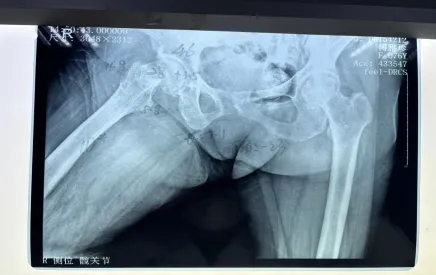

但不幸再次降臨,阿婆在家起床時不慎摔倒,右髖部疼痛難忍,經(jīng)過醫(yī)院檢查后確認(rèn),傅阿婆為右側(cè)股骨頸骨折。

阿婆住院后,羅院長立馬聯(lián)系內(nèi)科和麻醉科專家來會診,積極調(diào)整阿婆各項不理想指標(biāo),盡量將手術(shù)風(fēng)險降到最低。羅院長還針對阿婆病情特殊情況進(jìn)行一對一的計算機(jī)三維精準(zhǔn)規(guī)劃,精心打造出詳細(xì)的手術(shù)方案,經(jīng)過羅院長手術(shù)團(tuán)隊的努力,阿婆成功完成了機(jī)器人輔助下右側(cè)人工雙動股骨頭置換術(shù)。